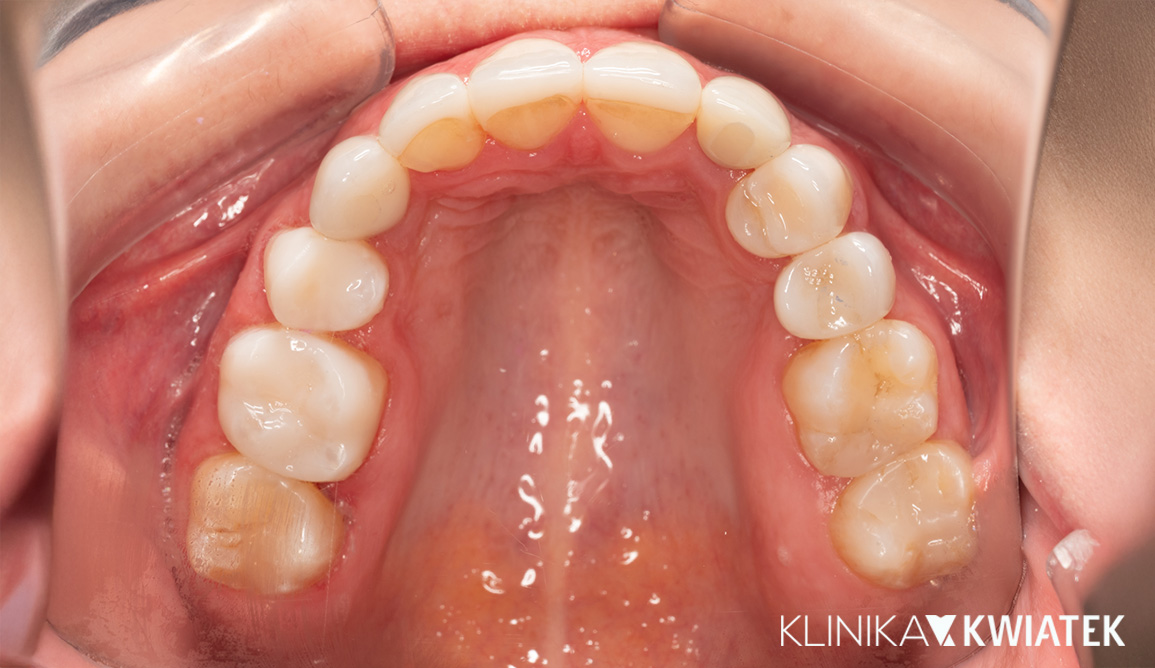

Kompleksowa transformacja uśmiechu po leczeniu ortodontycznym

Pacjentka zgłosiła się do kliniki po zakończeniu leczenia ortodontycznego nakładkami w innym gabinecie, w celu odbudowy brakującego zęba trzonowego. Po szczegółowej diagnostyce zaplanowano leczenie implantologiczne, protetyczne oraz periodontologiczne. Dzięki precyzyjnej pracy zespołu specjalistów uzyskano pełną odbudowę estetyki i funkcji – naturalny, harmonijny uśmiech oraz zdrowe, stabilne przyzębie.